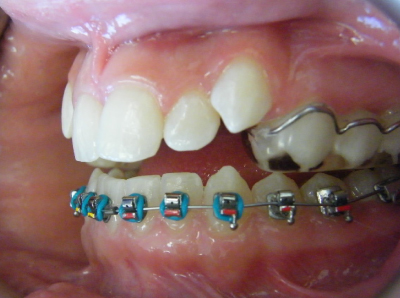

The first two sets of photos below are the before and after photos of a patient who had expansion of the upper jaw followed by upper and lower fixed braces. The third set of photos shows a patient with an expansion plate bonded to the upper teeth and lower fixed braces.